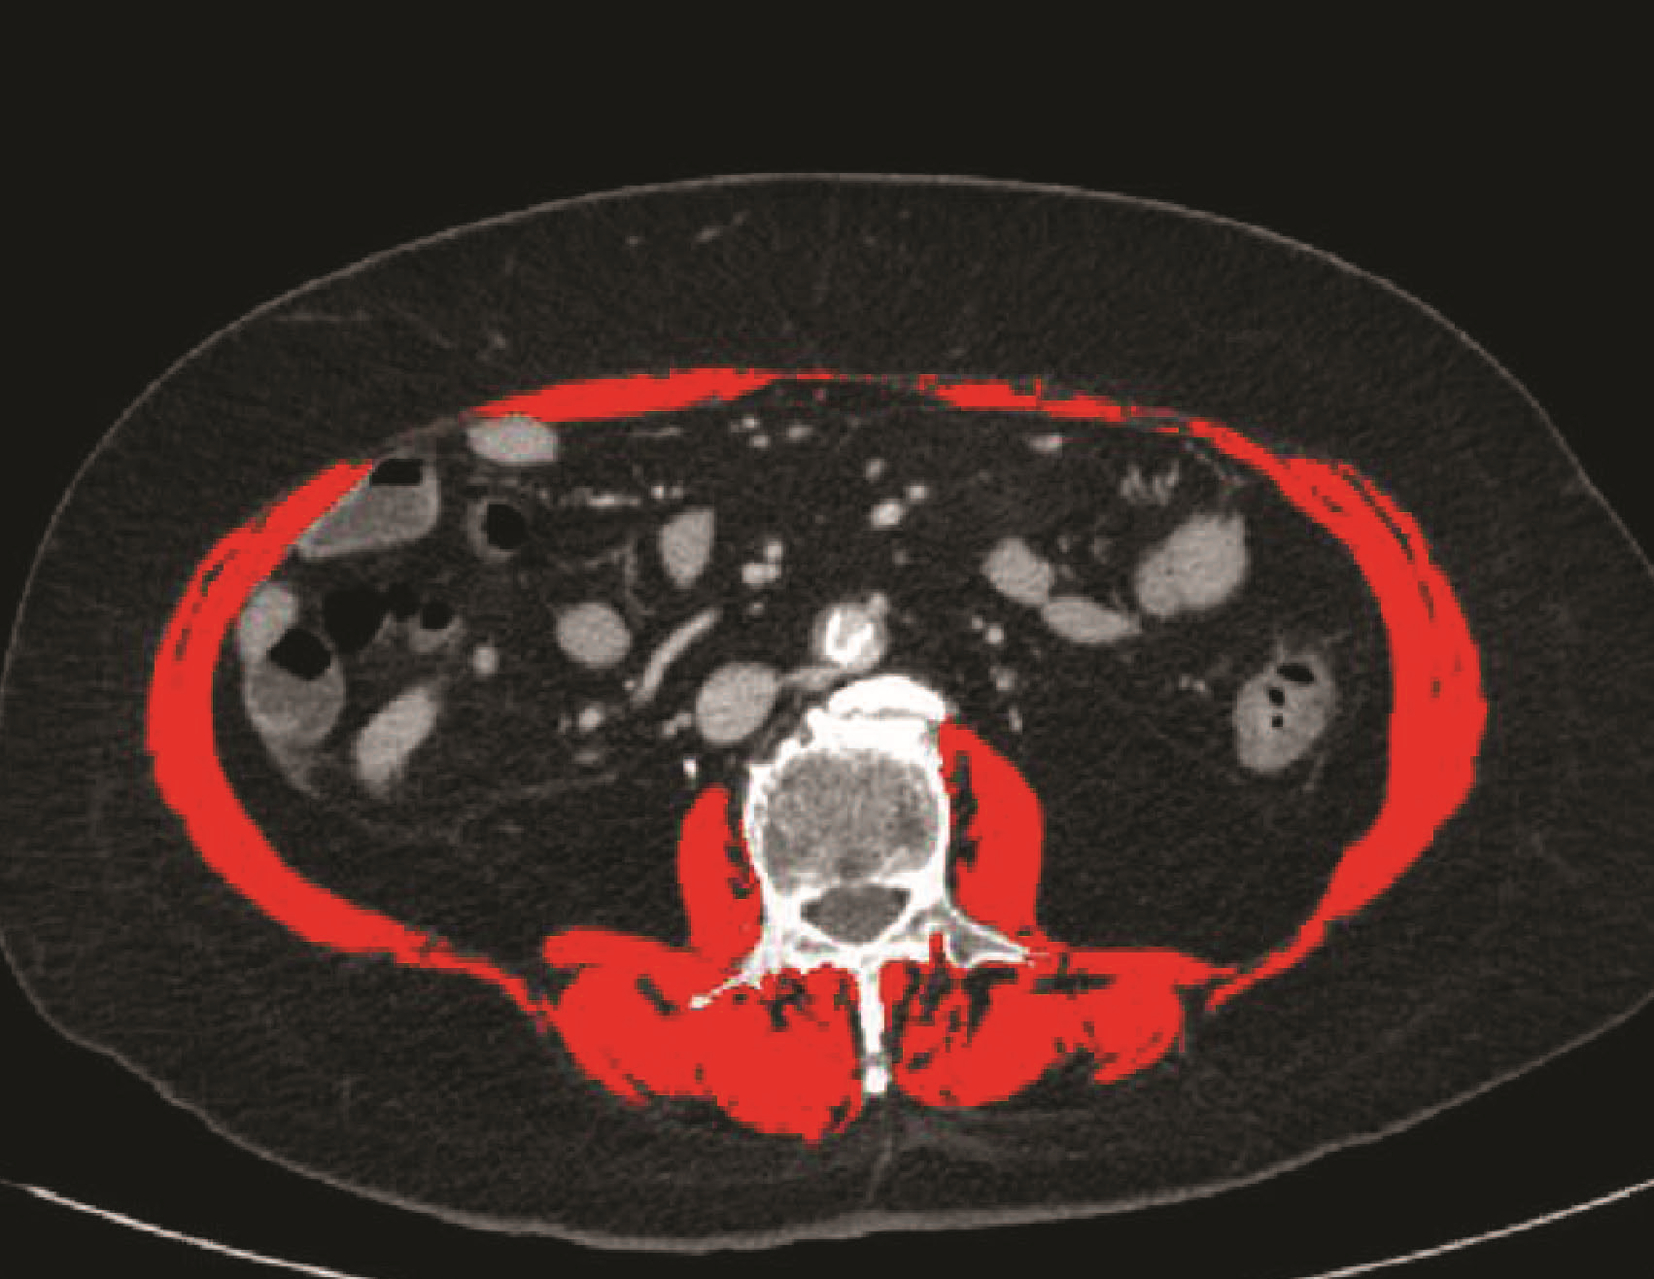

乙型肝炎肝硬化上消化道出血的ΔCT特征性表现及预测模型的建立

李俊杰, 孙岩岩, 李将宏, 郑虹

2022, 38(5): 1081-1085. DOI: 10.3969/j.issn.1001-5256.2022.05.020

摘要(1053) HTML (308) PDF (2671KB)(64)

摘要:

目的  本研究旨在寻找乙型肝炎肝硬化CT特征,建立肝硬化上消化道出血预测模型,预测出血风险。  方法  回顾性分析2015年1月—2021年6月天津市第一中心医院101例型肝炎肝硬化患者的数据,将其分为上消化道出血组(P=58)及非出血组(n=43)。比较两组间实验室检查以及强化CT检查测的平扫期、动脉期、门脉期以及静脉期的CT值,并计算各期间CT值的变化(ΔCT)。计量资料两组间的比较使用t检验或Mann-Whitney U检验;使用logistic回归分析方法,预测相关危险因素;通过计算受试者工作特征曲线下的面积评估模型辨别力,而模型校准则通过Hosmer-Lemeshow确定。在多变量logistic回归分析结果的基础上,使用Rstudio4.1.2软件的R包构建预测的列线图模型,并绘制相应的ROC曲线、校准曲线以及临床决策曲线。  结果  非出血组血清TBil、WBC、PLT水平与出血组比较,差异均有统计学意义(P值均<0.05);两组在肝-Plain、脾-P-Plain、脾-P-A ΔCT值存在统计学差异(P值均<0.05)。单因素logistic分析结果显示,白细胞(OR=0.770,95%CI:0.624~0952, P=0.016)、血小板(OR=0.979,95%CI:0.965~0.994, P=0.006)、肝脏平扫期(OR=1.142,95%CI:1.058~1.233, P=0.001)、脾脏门脉期-平扫ΔCT值(OR=0.979,95%CI:0.959~1.000, P=0.050)、脾脏门脉期-动脉期ΔCT值(OR=0.979,95%CI:0.944~0.994, P=0.015)在乙型肝炎肝硬化患者发生上消化道出血与未出血两者之间差异具有统计学意义。多因素logistic分析结果显示血小板(OR=0.968,95%CI:0.944~0.993, P=0.011)、肝脏平扫期(OR=1.148,95%CI:1.047~1.259, P=0.003)、脾脏门脉期-动脉期ΔCT值(OR=0.951,95%CI:0.908~0.995, P=0.030)为上消化道出血的独立危险因素。基于多因素logistic分析结果,构建了乙型肝炎肝硬化上消化道出血的预测模型并绘制校准曲线。该模型的受试者特征曲线下面积为0.801,cut-off值为0.433,其对应的敏感度是81.4%,特异度是77.6%。模型的校准曲线与理想曲线贴合良好。  结论  乙型肝炎肝硬化肝脏具有特殊的ΔCT变化,通过ΔCT构建的预测模型对于乙型肝炎肝硬化上消化道出血具有良好的预测能力。